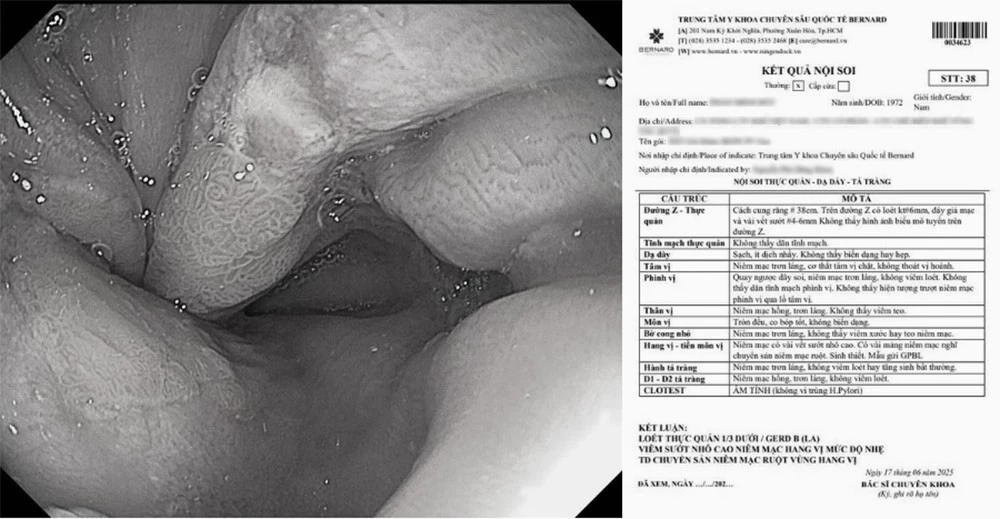

Nhằm làm sáng tỏ mối liên hệ giữa PBF và GERD, Bernard Healthcare đã thực hiện nghiên cứu trên 836 khách hàng Ningen Dock trong giai đoạn từ năm 2020 đến 2025, bao gồm 174 bệnh nhân GERD và 662 người đối chứng khỏe mạnh. Bộ dữ liệu thu thập rất toàn diện, bao gồm: kết quả nội soi tiêu hóa, chỉ số BMI, tỷ lệ mỡ cơ thể (PBF) đo bằng phương pháp y khoa, cùng khảo sát chi tiết về lối sống.

Kết quả nghiên cứu cho thấy, PBF có mối liên quan chặt chẽ với nguy cơ GERD hơn BMI. Mặc dù BMI vẫn hữu ích trong nhận diện GERD mức độ nhẹ (Grade A), nhưng PBF vượt trội trong dự báo các ca nặng (Grade B & C). Khi kết hợp PBF và BMI sẽ giúp tăng độ chính xác khi đánh giá nguy cơ mắc GERD. Đặc biệt, các yếu tố lối sống ảnh hưởng rõ rệt: Ăn nhiều thịt đỏ, ăn mặn, uống rượu bia, cà phê, hút thuốc, nước ngọt có ga, thói quen đi nằm ngay sau ăn làm tăng nguy cơ GERD. Ngược lại, ăn uống điều độ, nhiều rau xanh, tập thể dục thường xuyên và giữ khoảng cách 2–3 giờ giữa bữa tối – giờ ngủ giúp giảm nguy cơ GERD.